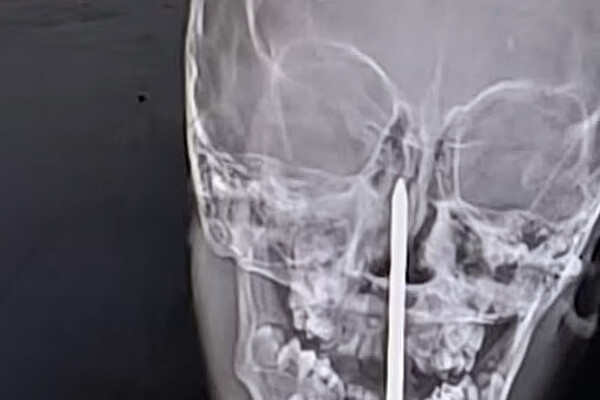

Семилетний мальчик из штата Раджастан перенес сложную нейрохирургическую операцию, во время которой врачи извлекли гвоздь длиной семь сантиметров из его мозга, пишет Daily Mail.

По данным местных СМИ, инцидент произошел, когда мальчик играл рядом со строительной площадкой, где споткнулся и упал носом на гвоздь. Его срочно доставили в больницу в Джайпуре, сделали компьютерную томографию и обнаружили, что инородный предмет почти на пять сантиметров проник в мозговую ткань.

Хирургическая бригада под руководством доктора Санкета Шармы провела более чем четырехчасовую операцию по удалению гвоздя. По словам врачей, чудом затронутыми оказались только лобные доли мозга, отвечающие в основном за когнитивные функции, а не за жизненно важные центры.